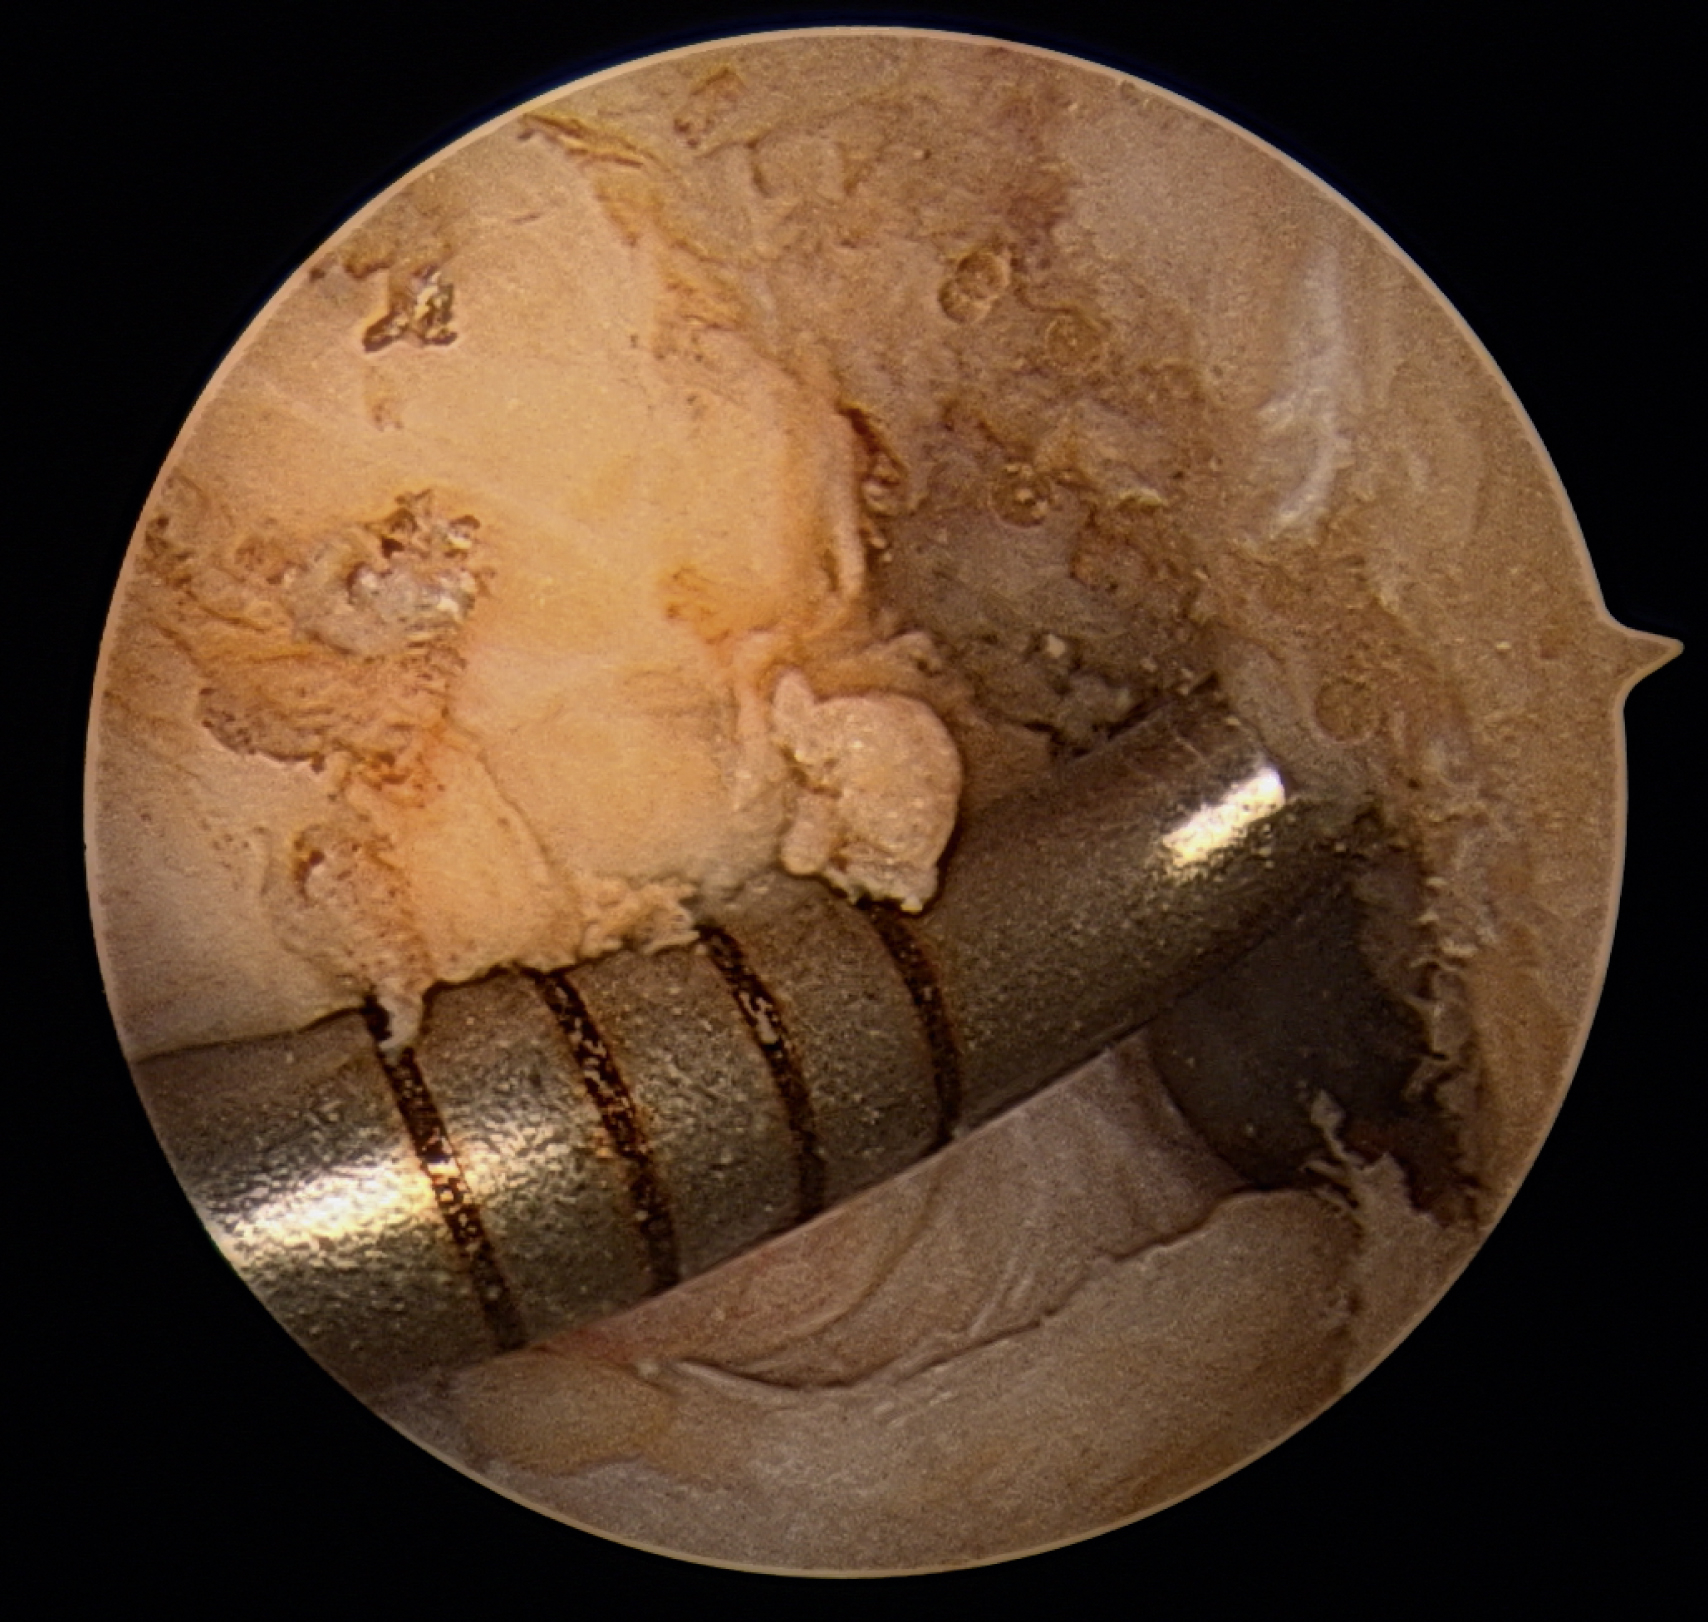

Tunnel Creation

A minimal notchplasty (2 mm) of the lateral wall will facilitate visualization, and a débridement of soft tissue from the lateral wall will also help locate the ACL center. After identifying the point for the femoral tunnel, an awl is used through the medial portal to create a pilot hole for reaming ( Fig. 49.5 ). It is helpful to verify the position of the pilot hole by visualization through the medial portal. The pilot hole should be approximately 8.5 mm (range 8.0–9.5 mm) up the lateral wall and slightly deep to the midpoint between the front and back of the notch ( Fig. 49.6 ).